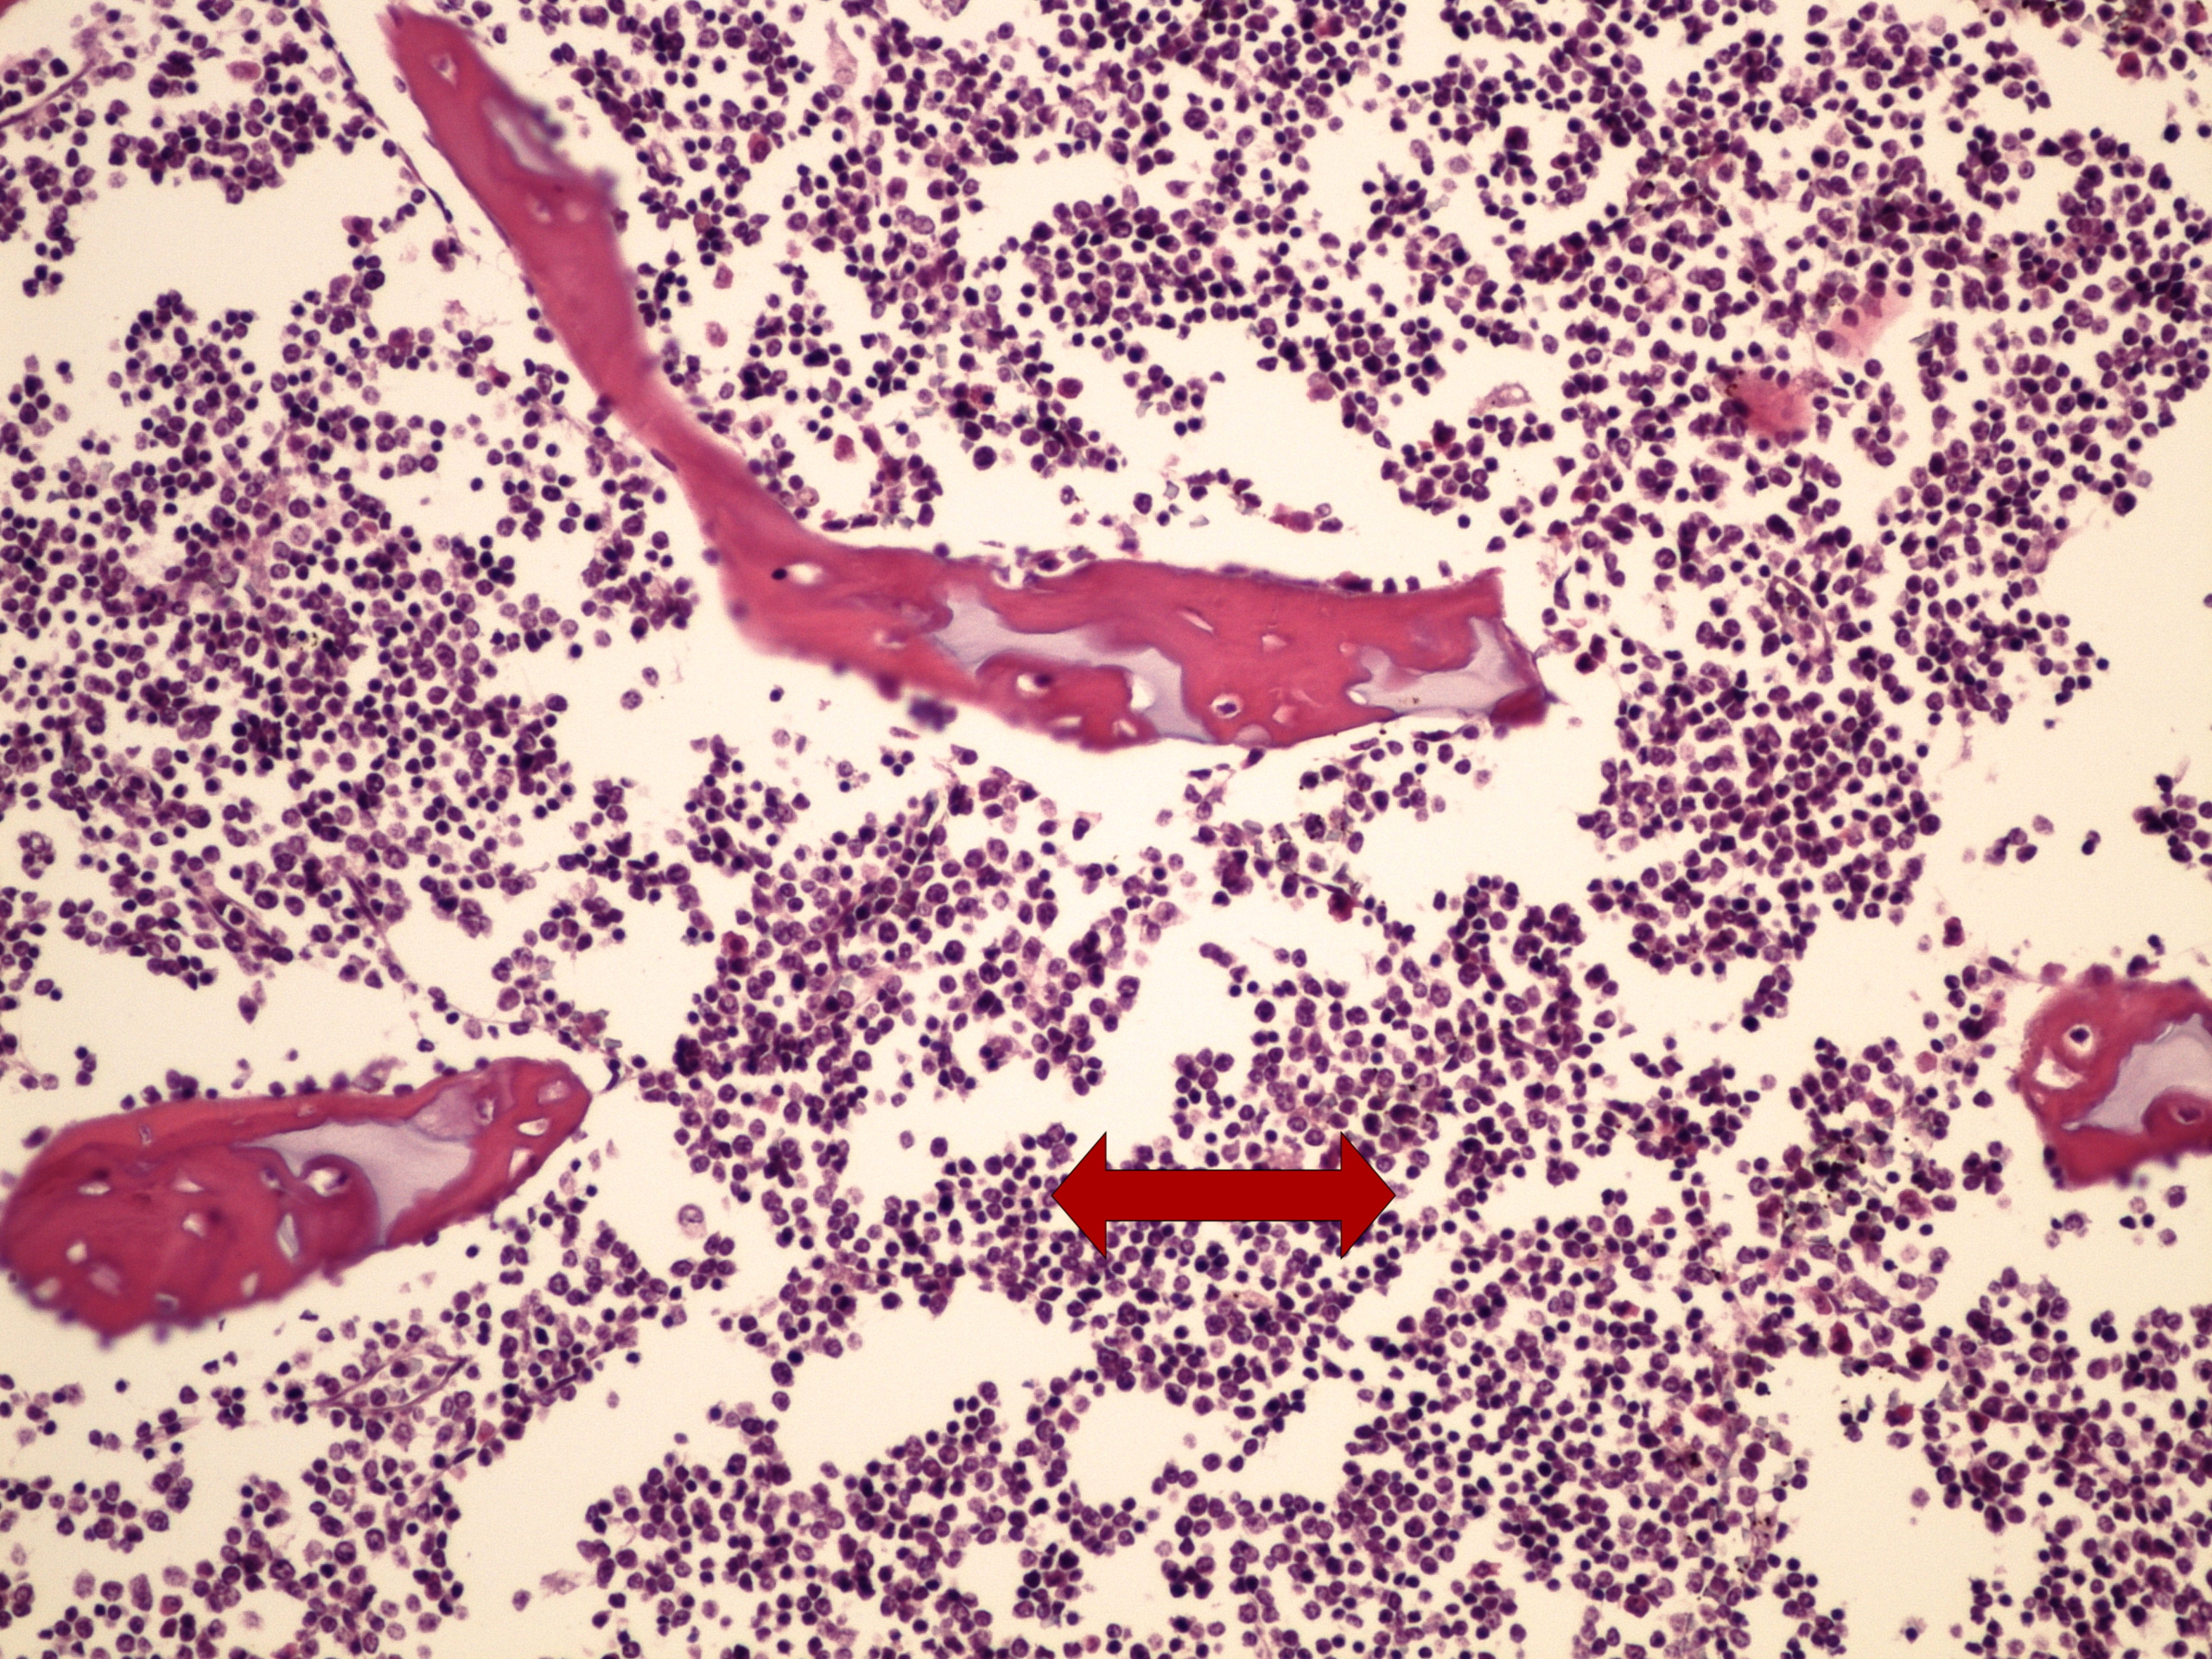

Preparát č.5 a č.6 - infiltrace kostní dřeně při CLL

Struktury

- peritrabekulární infiltrace malými lymfoidními elementy

- trabekuly